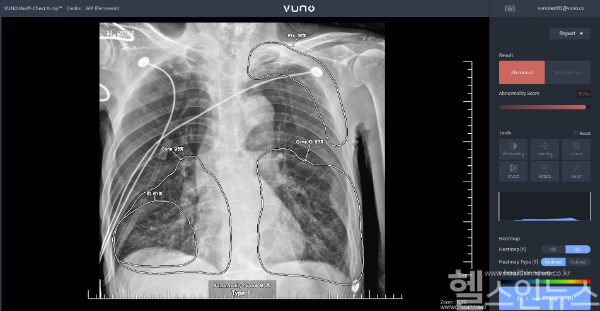

Chest X-ray는 흉부 X-ray 영상에서 결절, 경화, 간질성 음영, 흉막 삼출, 기흉 등 5가지 이상 소견을 검출하고, 이를 기반으로 폐렴과 폐결핵을 선별하는 진단 보조 AI 소프트웨어다. 이미 안전성과 임상 잠재력을 인정받은 제품으로, 이번 고시를 통해 실제 진료 환경에서 본격 활용될 수 있게 됐다.